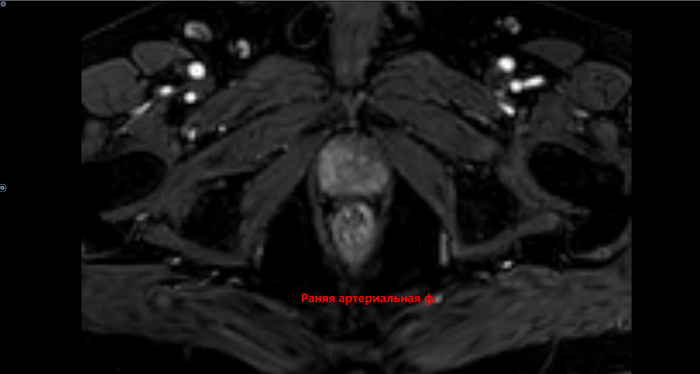

Преимущественно в периферической зоне предстательной железы, определяются участки, размерами 21х11мм,28х8мм, с 3 до 6 часов, с 6 до 11 часов условного циферблата гиперинтенсивного МР сигнала на DWI B1000,гипоинтенсивного сигнала на ИКД карте-соответствуют истинному ограничению диффузии. С быстрым накоплением контраста в раннюю артериальную фазу контрастирования, с последующим вымыванием контраста с позднюю артериальную фазу. В теле L5 позвонка -участок гипоинтенсивного сигнала на Т2 с не четкими, не ровными контурами,d 2.9см. Заключение: МР картина рака предстательной железы, V класс по PIRADS v.2.1. Участок в теле L5 позвонка наиболее соответствует mts. Состояние после троакарной цистостомии, биорхэктомии.